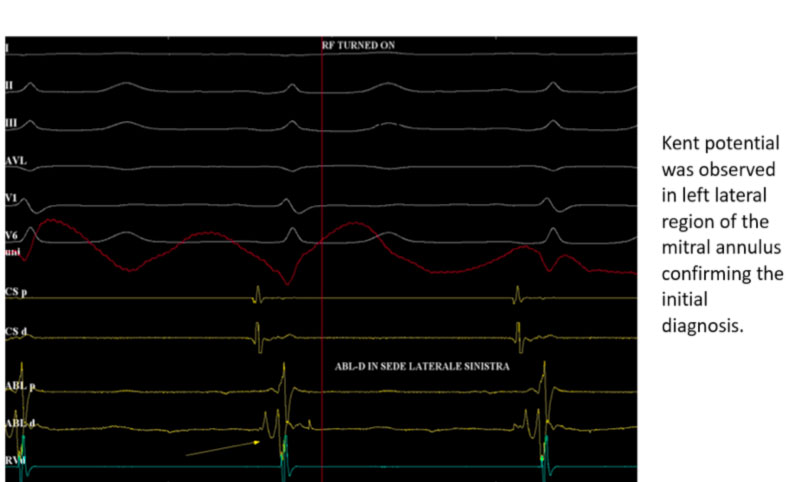

Nel caso di cui sopra ad esempio si posiziona per via trans-aortica il catetere ablatore in posizione laterale sinistra e si registra sul dipolo distale il tipico potenziale di Kent

Quando la pre-eccitazione non è massima, la stimolazione atriale rapida o l’adenosina I.V. può essere utilizzata per ottenere la pre-eccitazione completa in modo da migliorare l’accuratezza della localizzazione. Ciò è particolarmente utile nelle vie accessorie laterali di sinistra in cui la pre-eccitazione può essere migliorata con la stimolazione atriale sinistra (dal seno coronarico, CS, catetere). I criteri dell’elettrogramma intracardiaco (8) utilizzati per identificare i siti target appropriati per l’ablazione delle vie manifeste comprendono la presenza di un potenziale lungo al avia accessoria (Fig. 5), l’inizio precoce dell’attivazione ventricolare locale rispetto all’insorgenza dell’onda delta, la stabilità dell’elettrogramma e l’attività elettrica continua anterograda (elettrodi atriali e ventricolari fusi).

Il primo sito di attivazione ventricolare durante la preeccitazione manifesta (ritmo sinusale preeccitato, AVRT antidromico) identifica il sito di inserzione ventricolare della via accessoria. I criteri del sito target per l’ablazione durante la mappatura anterogrado includono: 1) potenziale AP (potenziale Kent), 2) prima attivazione ventricolare locale relativa all’insorgenza dell’onda delta (pre-delta) e 3) fusione di elettrogrammi atriali e ventricolari. I potenziali del percorso accessorio riflettono una rapida attivazione locale della via accessoria e sono deflessioni acute e ad alta frequenza tra gli elettrogrammi atriali e ventricolari che precedono l’insorgenza dell’onda delta. Quanto più l’elettrogramma ventricolare locale sul catetere di ablazione precede l’insorgenza dell’onda delta, maggiore è la probabilità di successo.